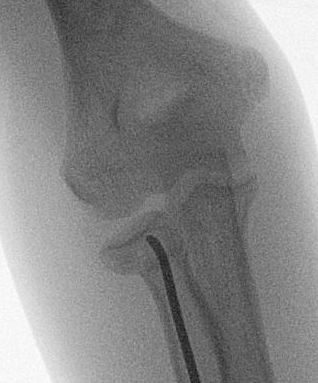

Xray

Displaced and angulated radial neck fracture